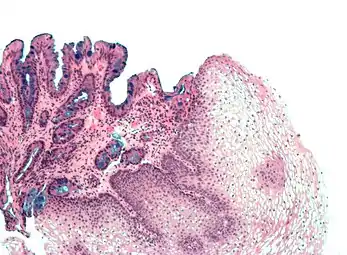

Micrograph showing Barrett's esophagus - columnar epithelia with goblet cells - on the left side of image; and normal stratified squamous epithelium on the right side of image Alcian blue stain

High-magnification micrograph of Barrett's esophagus showing the characteristic goblet cells, Alcian blue stain

Both macroscopic (from endoscopy) and microscopic positive findings are required to make a diagnosis. Barrett's esophagus is marked by the presence of columnar epithelia in the lower esophagus, replacing the normal squamous cell epitheliuman example of metaplasia. The secretory columnar epithelium may be more able to withstand the erosive action of the gastric secretions; however, this metaplasia confers an increased risk of adenocarcinoma.[15]

Intestinal metaplasia

The presence of goblet cells, called intestinal metaplasia, is necessary to make a diagnosis of Barrett's esophagus. This frequently occurs in the presence of other metaplastic columnar cells, but only the presence of goblet cells is diagnostic. The metaplasia is grossly visible through a gastroscope, but biopsy specimens must be examined under a microscope to determine whether cells are gastric or colonic in nature. Colonic metaplasia is usually identified by finding goblet cells in the epithelium and is necessary for the true diagnosis.

Many histologic mimics of Barrett's esophagus are known (i.e. goblet cells occurring in the transitional epithelium of normal esophageal submucosal gland ducts, "pseudogoblet cells" in which abundant foveolar [gastric] type mucin simulates the acid mucin true goblet cells). Assessment of relationship to submucosal glands and transitional-type epithelium with examination of multiple levels through the tissue may allow the pathologist to reliably distinguish between goblet cells of submucosal gland ducts and true Barrett's esophagus (specialized columnar metaplasia). The histochemical stain Alcian blue pH 2.5 is also frequently used to distinguish true intestinal-type mucins from their histologic mimics. Recently, immunohistochemical analysis with antibodies to CDX-2 (specific for mid and hindgut intestinal derivation) has also been used to identify true intestinal-type metaplastic cells. The protein AGR2 is elevated in Barrett's esophagus[17] and can be used as a biomarker for distinguishing Barrett epithelium from normal esophageal epithelium.[18]